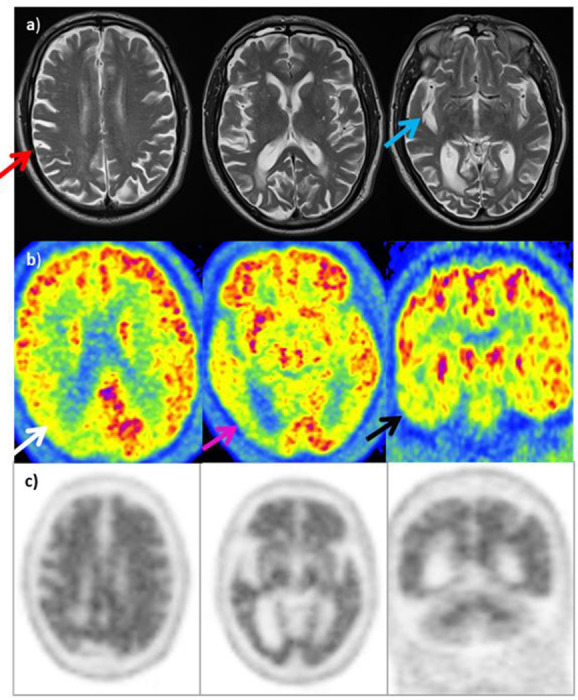

Variante Logopenica della PPA (lvPPA) – Variante linguistica

La lvPPA (Afasia Primaria Progressiva variante logopenica) è quasi invariabilmente causata dalla patologia Alzheimer. Il pattern metabolico è fortemente asimmetrico, con un ipometabolismo localizzato nella regione temporo-parietale sinistra, in particolare attorno al giro temporale superiore posteriore e al giro angolare. Questo riflette clinicamente l’incapacità di recuperare le parole e la compromissione della memoria di lavoro fonologica.

(C) Variante logopenica dell’afasia primaria progressiva (lvPPA): mostra ipometabolismo nelle aree temporali e parietali sinistre.

Demenza vascolare (VaD)

Nella VaD, la PET FDG rivela spesso un pattern asimmetrico e focale, con aree di ipometabolismo “a macchia” che non seguono la distribuzione dei circuiti neurodegenerativi classici. Spesso si osserva il coinvolgimento di strutture sottocorticali come i gangli della base e il talamo, oltre alla possibile presenza di diaschisi cerebellare crociata (riduzione del metabolismo in un emisfero cerebellare secondaria a un insulto corticale controlaterale).